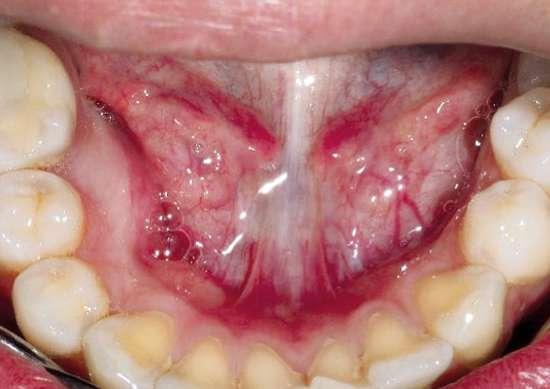

A la exploración intraoral se observaba abombamiento de la cortical lingual en la zona derecha de la mandíbula (Fig. 1). Se realizó un CBCT donde se pudo observar que el diente supernumerario tenía aspecto de premolar, estando alojado de manera

cabalgada entre lingual y vestibular (la corona del diente se encontraba por la zona linguodistal del 44, mientras su raíz se localizaba a nivel interradicular, en íntimo contacto con el nervio dentario inferior.

Dada la cercanía a las raíces de los dientes adyacentes y el riesgo de rizólisis de las mismas, se optó por realizar la exodoncia, utilizando para ello anestesia local de la zona (Fig. 2).

Tal y como se puede observar en las imágenes (Fig. 3 y 4) se realizó una incisión sulcular siguiendo el surco gingivodentario lingual sin descargas para despegar un colgajo a espesor total que facilitó un campo quirúrgico suficiente como para poder realizar la ostectomía hasta descubrir la corona del diente (Fig. 5).

La ostectomía se realizó de manera cuidadosa, tanto con el colgajo y las estructuras del suelo de boca, como con los dientes adyacentes y sus raíces. En este caso el diente no requirió odontosección, por lo que su exodoncia pudo ser completada usando un botador recto y unas pinzas adson para su retirada del alveolo (Fig. 6).

Figuras 1 y 2. Situación inicial y anestesia. Figuras 3 y 4. Incisión y despegamiento del colgajo lingual festoneado.

1 2

Figuras 5 y 6. Ostectomía y exodoncia con botador tipo elevador recto.